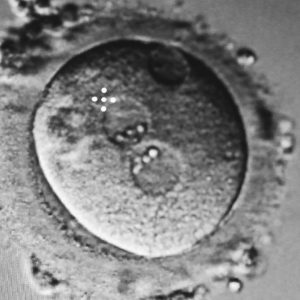

• Fertilização in vitro (ICSI);

• Transferência de embriões à fresco;

• 1 Palheta de congelamento de embriões;